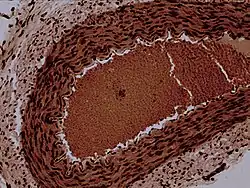

![]() شرين أرنب مكبر 100X شرين أرنب مكبر 100X | |

يتكون جدار الشرين مثل بنية شريان حيث نفرق بين غلالة باطنة وغلالة وسطانية وطبقة خارجية Tunica Adventitia.

تكون الغلالة الوسطانية في الشرين رقيقة ولكن ما يوجد بها من عضلات ملساء يمكن ان تقفلها تماما ؛ في حين أن غلق العضلات لشرايين كبيرة ليس ممكنا. بهذا التحكم في الإغلاق يمكن مرور الدم في الشعيرات التالية ويعمل هذا التكم على خفض معدل مرور الدم في أنسجة هادئة.

يبلغ اتساع الشرينات نحو 20 ميكرومتر . وبعض المختصين يعرّفونها بأنها الأوعية الدموية التي لها طبقة واحدة من الخلايا العضلية الملساء ، بعكس الشرايين الكبيرة التي تتكون من عدة طبقات من العضلات الملساء ؛ [2] ومع ذلك فتعتبر شرينات قبلها أكبر، ذات طبقتين أو ثلاثة من خلايا العضلات الملساء، تعتبر أيضا شرينات وليست شرايين.[3]